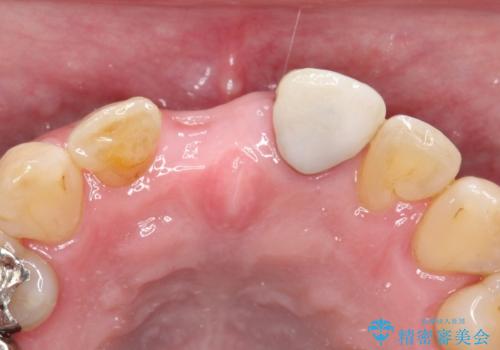

- 矯正治療終了後の患者様です。

前歯が欠損しており、ブリッジでの修復を希望されましたので、オールセラミッククラウン(スタンダード)で治療を行いました。